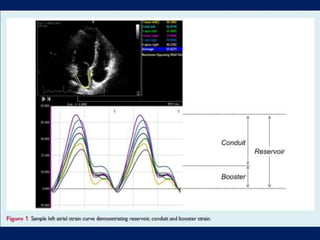

LA strain during

• the reservoir phase (LAS r) = difference of the strain value at

mitral valve opening minus ventricular end – diastole

(positive value)

• the conduit phase (LAScd) = difference of the strain value at

the onset of atrial contraction minus mitral valve opening

(negative value)

• In AF, LAScd = LASr but with a negative sign

• the contraction or booster phase, measured in patients only

in sinus rhythm, difference of the strain value at ventricular

end diastole minus onset of atrial contraction (negative

value).